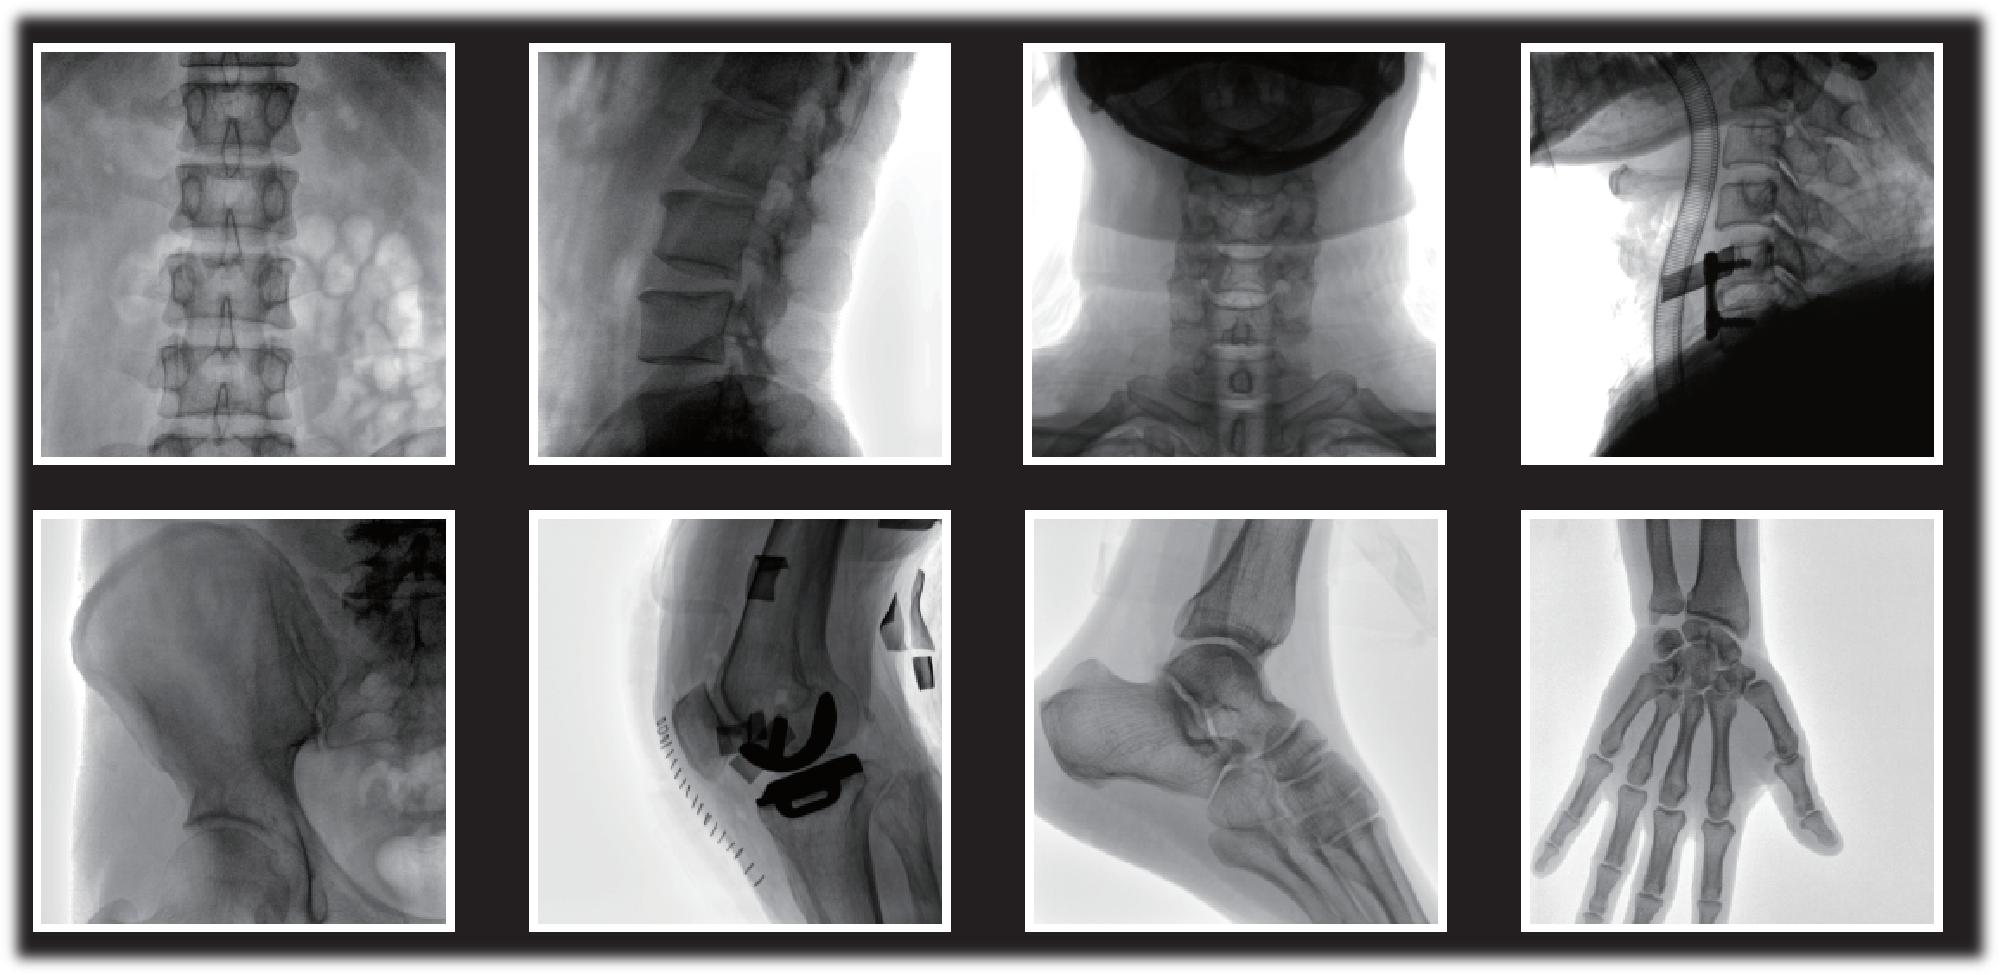

【產(chǎn)品臨床圖片】